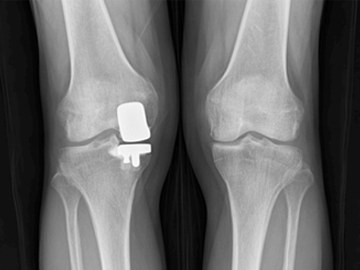

무릎인공관절 전체치환술

수술

치료

ㆍ환자 동의를 받은 자료이며, 이미지 사진은 실물과 다를 수 있습니다.

ㆍ전 : 2020.07.27 / 후 : 2020.08.13 엑스레이 전,후 사진입니다.